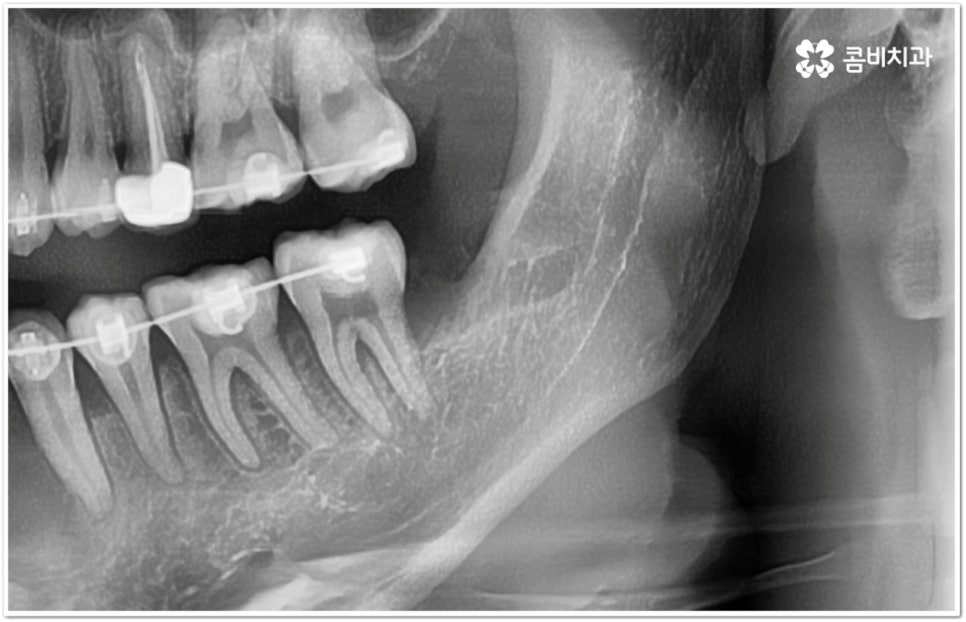

만약 똑바로 자라나고 관리가 용이하며 마주보는 대합치 역시 정상적으로 맹출되었다면 사랑니를 꼭 발치할 필요는 없을 거예요. 그러나 보통 사랑니는 사람의 치아 중에 가장 마지막에 나오는 치아라서 이미 구강 내 공간이 비좁은 상태이기 때문에 비스듬하게 자리를 잡고 일부분만 맹출이 되는 경우가 많이 있어요. 보통 머리가 앞쪽으로 기울어진 근심위로 자리잡는 케이스가 가장 많으며 그 밖에도 치아 머리가 뒤쪽으로 기울어져 있거나 혀쪽, 볼쪽으로 누운 케이스, 아예 옆으로 완전히 누운 케이스 등도 발견되고 있는데요.

잇몸에 반쯤 덮힌 채로 삐뚤게 나온 사랑니는 칫솔질을 제대로 하기 어렵고 위생 관리가 잘 되지 않아 주변 잇몸에 염증이 생기기 쉬우며 어금니까지 충치가 번질 위험이 높아지게 되어 구강 건강 관리 및 예방 차원에서 발치 처치를 해주실 필요가 있어요. 발치 난이도는 사랑니의 경사 각도와 방향 및 치아 뿌리의 길이와 개수, 사랑니 뒤쪽 턱 뼈의 각도 및 형태, 하치조 신경 또는 상악동까지의 거리 등에 따라서 달라질 수 있습니다.

이때 아래사랑니발치 의 경우 아래턱 부근을 지나가는 큰 신경인 하치조 신경을 건드리지 않고 조심스럽게 사랑니만 제거해야 하기 때문에 3D-CT 등 정밀 검진 기계를 통해 사랑니의 매복 위치, 깊이, 각도 등의 상태와 신경까지의 거리 등을 먼저 꼼꼼하게 파악한 후에 발치를 해 줄 필요가 있는데요. 만약 완전히 매복되어 있다면 사랑니 주변에 함치성 낭종이 발생할 수도 있는데 이로 인해 주변 치조골이 파괴되고 어금니 쪽으로 병변이 확산되면 결국 치아를 상실하게 되거나 턱뼈가 약해져서 작은 충격에도 부러지는 현상이 발생할 가능성도 있으므로 될 수 있는대로 치료 시기를 놓치지 않는 것이 중요한 포인트라고 할 수 있어요.

이와 같이 환자분들의 상황에 따라서 잇몸 절개 및 골삭제 후 사랑니를 조각내어 빼내야 하는 고난도의 과정들이 필요할 수도 있기 때문에 아래사랑니발치 시 관련 임상 경험이 많고 섬세한 기술력을 가지고 있는 숙련된 의료진과 함께 하시길 권유드리고 있습니다.

관리하기 까다롭기 때문에 위 아래사랑니발치 를 해 주는 것이 보통이긴 하지만 간혹 사고로 어금니를 상실하거나 유전적으로 어금니가 없으신 분들의 경우 교정 치료를 통해 어금니 대신 사용하는 사례가 있으니 필요하다면 발치 결정 전에 꼼꼼하게 검진을 받아보실 필요가 있어요.

모든 경우에 사랑니가 어금니를 대신할 수는 없으며 사랑니로 어금니를 대체하기 위해서는 사랑니의 상태, 이동 가능 공간, 주변 구조물 및 전체 구강 구조 등 환자분들의 상황을 먼저 면밀하게 살펴본 후 교정 치료 계획을 세심하게 세워 잇몸과 사랑니의 손상 없이 치료할 필요가 있으므로 고난도 과정에 맞게 술자의 높은 숙련도가 요구되는 만큼 노하우가 풍부한 의료진을 선택하시길 권유드리고 있습니다.